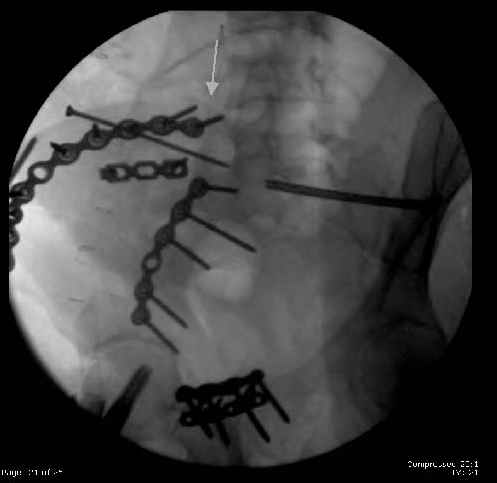

Here are the postop fluoros.

Fluoroed L SI joint and it seemed stable, but wide. So, applied c-clamp to try to squeeze down L SI joint (and note, on the last slide attached, that it's still wide), and got it closer. Single perc Iliosacral screw 40mm thread.